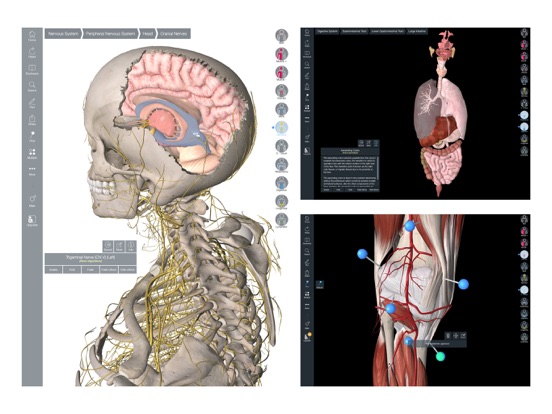

Downloading Essential Anatomy 5 IPA for iOS is a convenient and useful way to explore the world of human anatomy right from the comfort of your iPhone or iPad. This app provides a comprehensive and detailed view of the human body, allowing users to interact with various systems and structures. With stunning 3D graphics, it offers a visually captivating experience that aids in understanding and learning about the complexities of the human body. Whether you are a medical student, healthcare professional, or someone with a general interest in anatomy, Essential Anatomy 5 IPA is a must-have app that provides a wealth of knowledge at your fingertips. The app’s intuitive interface and easy navigation make it accessible to users of all levels of expertise. With just a few taps, you can delve into different layers of the body, explore various organs, muscles, and bones, and gain a deeper understanding of human anatomy. Download Essential Anatomy 5 IPA today and elevate your knowledge and appreciation of the human body.

The Essential Anatomy 5 IPA for iPhone is an incredible tool for medical students, professionals, and anyone interested in learning more about the human body. This app provides a comprehensive and detailed 3D model of the human anatomy, allowing users to explore and study different parts of the body with ease. With its user-friendly interface and interactive features, users can zoom in, rotate, and examine every angle of the human body, from bones and muscles to organs and systems. The app also provides in-depth information about each structure, making it a valuable resource for studying and understanding the intricacies of human anatomy. Whether you’re a medical student preparing for exams or simply curious about the wonders of the human body, the Essential Anatomy 5 IPA for iPhone is an essential tool to have at your fingertips.

Essential Anatomy 5 IPA MOD IOS is a revolutionary app that has changed the way we learn about the human body. With its advanced features and stunning visuals, this app provides an immersive and interactive experience for users. Whether you are a medical student, healthcare professional, or simply interested in learning about anatomy, Essential Anatomy 5 is a must-have tool. It offers a comprehensive library of detailed 3D models, allowing users to explore every aspect of the human body. From the skeletal system to the muscular system, nervous system to cardiovascular system, this app covers it all. Additionally, it provides in-depth information on each structure, including names, functions, and clinical relevance. With its user-friendly interface and intuitive controls, navigating through the app is a breeze. Overall, Essential Anatomy 5 IPA MOD IOS is an essential resource that brings anatomy to life, making it an invaluable tool for anyone interested in the human body.

This app provides a comprehensive and detailed 3D representation of the human body. With over 8,200 anatomical structures, including muscles, bones, organs, and more, it offers a level of accuracy and depth that is unparalleled. Whether you are studying for an exam or explaining a medical condition to a patient, Essential Anatomy 5 IPA has the information you need.

Essential Anatomy 5 IPA allows users to interact with the 3D models, zooming in and rotating them to explore every angle. The user-friendly interface makes navigating through the app a breeze, and the intuitive controls ensure that anyone, regardless of their level of expertise, can easily explore and understand the complex anatomical structures.

One of the standout features of Essential Anatomy 5 IPA is its ability to showcase cross-sectional views of the body. This enables users to see the internal structures and their relationships with each other, providing a deeper understanding of the body’s intricate systems. This feature is particularly useful for students learning about the different body cavities or professionals wanting to explain surgical procedures to their patients.